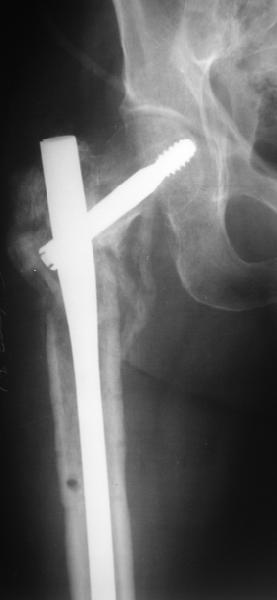

В приложении пример пациента, близкого по картине к тому, что представил Виктор (варус и смещение периферического отломка на поперечник кзади). Сделали как раз то, что Виктор исходно намеревался - аппаратная коррекция и затем гамма.